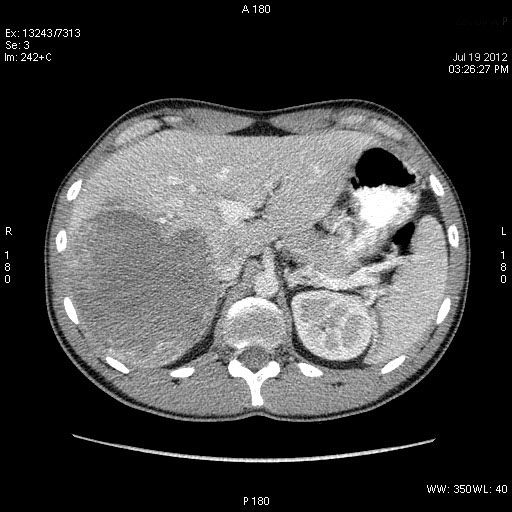

КТ через день

se000.jpg

se001.jpg

se002.jpg

Что-то не укладывается именно ультразвуковая картирка в абсцесс печени.

После КТ хирурги заказали дренирование "абсцесса".

Выполнена диагностическая пункция из 4х участков, получена только кровь.